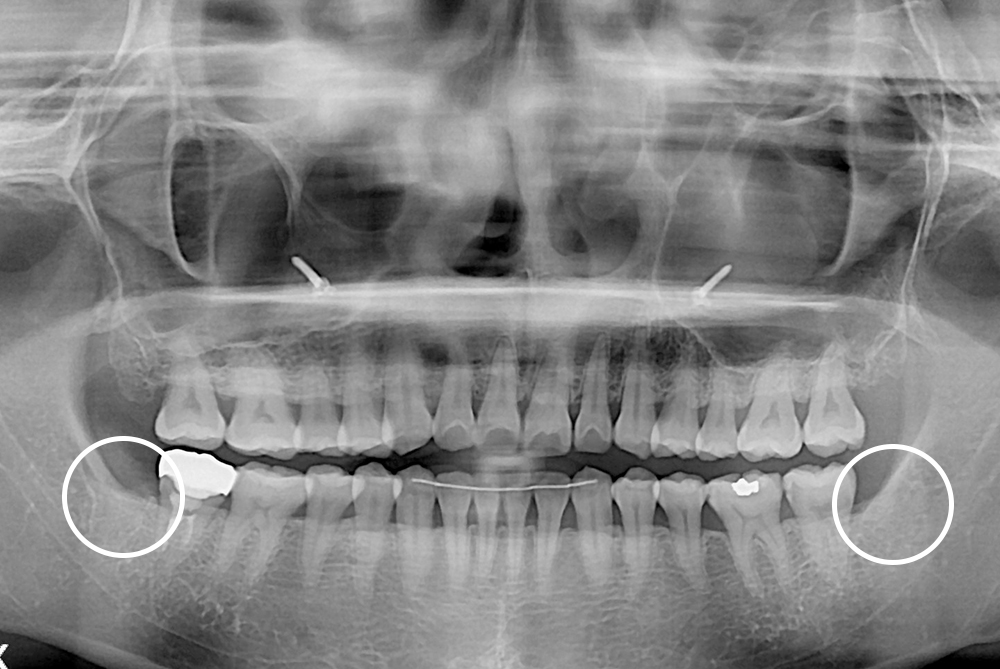

[사랑니] 매복 사랑니 발치

치료전 : 2020-01-14